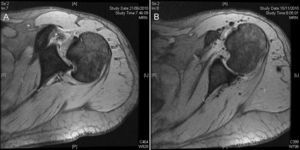

Fue trasladado al hospital más próximo y valorado por un médico de urgencias; se le realizaron radiografías que se consideraron normales y se diagnosticó una contusión de hombro y se remitió a su médico de atención primaria para control de la evolución. Tras 6 semanas el paciente no evolucionaba bien y se remite a consultas externas de traumatología. El paciente presentaba dolor y gran limitación funcional, con una flexión de 80°, abducción de 70° y 0° de rotación externa, con artrofia del deltoides y del infraespinoso y con actitud antiálgica en rotación interna. En la radiografía simple se diagnosticó una luxación posterior de hombro y se solicitó una RMN urgente, que mostraba una luxación posterior bloqueada del hombro derecho con un defecto óseo anterior en la cabeza humeral y una lesión del labrum posterior (fig. 1A). El paciente se intervino a los 2 días de la visita en consultas externas de traumatología.

Caso 1, hombro derecho. A. Imagen de la resonancia magnética preoperatoria donde podemos ver la luxación posterior del hombro bloqueado, la lesión de Hill Sachs inversa y la lesión de Bankart inversa. B. Imagen de la RM después de 5 meses de la cirugía artroscópica. Podemos ver el tendón subescapular llenando el defecto de hueso de la cabeza del húmero, el labrum posterior cicatrizado y la cabeza humeral centrada en la cavidad glenoidea.

En la RMN de control a los 5 meses se puede apreciar la cabeza humeral centrada en la glena, el mantenimiento del espacio glenohumeral y el subescapular rellenando el defecto óseo (fig. 1B).